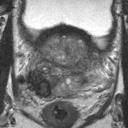

We present a novel technique to discover and exploit weak causal signals directly from images via neural networks for classification purposes. This way, we model how the presence of a feature in one part of the image affects the appearance of another feature in a different part of the image. Our method consists of a convolutional neural network backbone and a causality-factors extractor module, which computes weights to enhance each feature map according to its causal influence in the scene. We developed different architecture variants and empirically evaluated all of our models on two public datasets of prostate MRI images and breast histopathology slides for cancer diagnosis. To confirm our quantitative results, we conduct ablation studies and investigate the explainability of our models via class activation maps. Our findings show that our lightweight block extracts meaningful information and improves the overall classification, together with producing more robust predictions that focus on relevant parts of the image. That is crucial in medical imaging, where accurate and reliable classifications are essential for effective diagnosis and treatment planning.